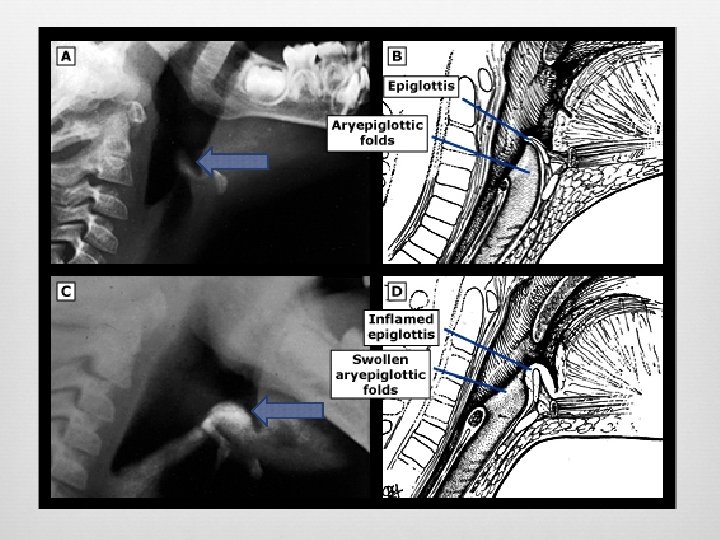

Epiglottitis Enlarged epiglottis Loss of valecular airspace Thickened aryepiglotic folds Distended hypopharynx Straightening of the cervical spine Sensitivity (38 -88%) Specificity (78%) Croup and epiglottitis: a radiologic study. AU Stankiewicz JA; Bowes AK SO Laryngoscope 1985 Oct; 95(10): 1159 -60. Epiglottitis and croup. AU Sobol SE; Zapata S SO Otolaryngol Clin North Am. 2008 Jun; 41(3): 551 -66, ix. Adult epiglottitis: the Toronto Hospital experience. AU Solomon P; Weisbrod M; Irish JC; Gullane PJ SO J Otolaryngol. 1998 Dec; 27(6): 332 -6.

Adult Epiglottitis Radiographic Criteria Epiglottic height-to-width ratio >0. 6 Epiglottic to C 4 vertebral body width ratio >0. 33 Aryepiglottic fold to C 3 vertebral body width ratio >0. 35 Prevertebral soft-tissue to C 4 vertebral body width ratio >0. 25 Hypopharyngeal airway to C 4 vertebral body width ratio >1. 5